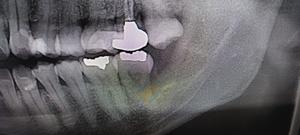

歯の詰め物(金属・銀歯)や薬剤の影響

古い銀歯や金属製クラウンから金属イオンが溶出し、口腔粘膜との接触でアレルギー反応が生じる場合があります。クロム・ニッケル・金・水銀などが原因物質となることがあり、金属アレルギーのある人は特に注意が必要です。

組織検査(生検)が必要なケースとは?

白斑が厚く、患部が硬い、出血しやすい

痛みが強く、潰瘍がある

がん化のリスクを排除したい場合

このような場合には粘膜の一部を採取する生体検査(生検)が行われます。